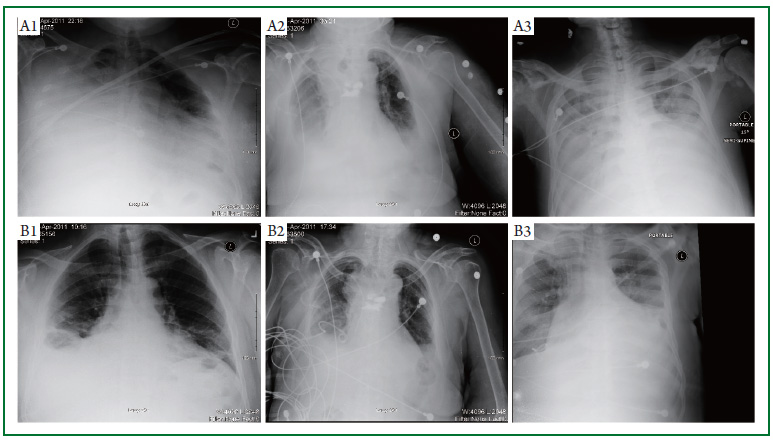

Computed tomography ct scan of the chest demonstrated the pigtail catheter tracking through the right middle and lower lobes reaching the posterior pleural space. Pneumothorax chest trauma pleur. Extubation will be done when the lung reaches full expansion. Ng tube tip 10 cm distal to the gastro esophageal junction.

After accidental dislodgement of the catheter it was replaced and the following day a chest x ray cxr demonstrated diffuse subcutaneous emphysema. Pharyngeal or esophageal perforation. Indication the indications are wide and can include 1. It is mainly inserted to treat pneumothorax.

This video demonstrates ultrasound guided placement of a small bore pigtail c. The intercostal catheter icc or chest tube is a tube inserted into the pleural space to drain gas or fluid. These products are available in a variety of sizes and design configurations. Follow up and extubation after chest tube or pigtail catheter insertion.